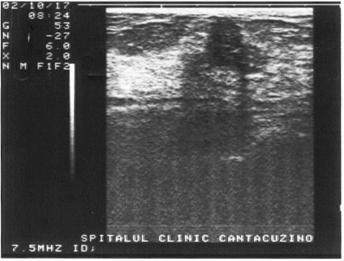

UMBRA ACUSTICA (CONUL DE UMBRA)

Este expresia unei atenuari si a unei reflectari maximale si apare in toate situatiile in care fasciculul de ultrasunete intalneste o structura foarte densa cum ar fi osul sau calculii. Distal de acesta nu mai exista ultrasunete, aspectul final fiind acela al unei "non imagini"; lipsa de ecouri se prezinta ca o structura liniara, de culoare neagra, denumita "con de umbra posterior".

Figura 18. Con de umbra in litiaza renala

Figura 19. Con de umbra posterioara in litiaza biliara